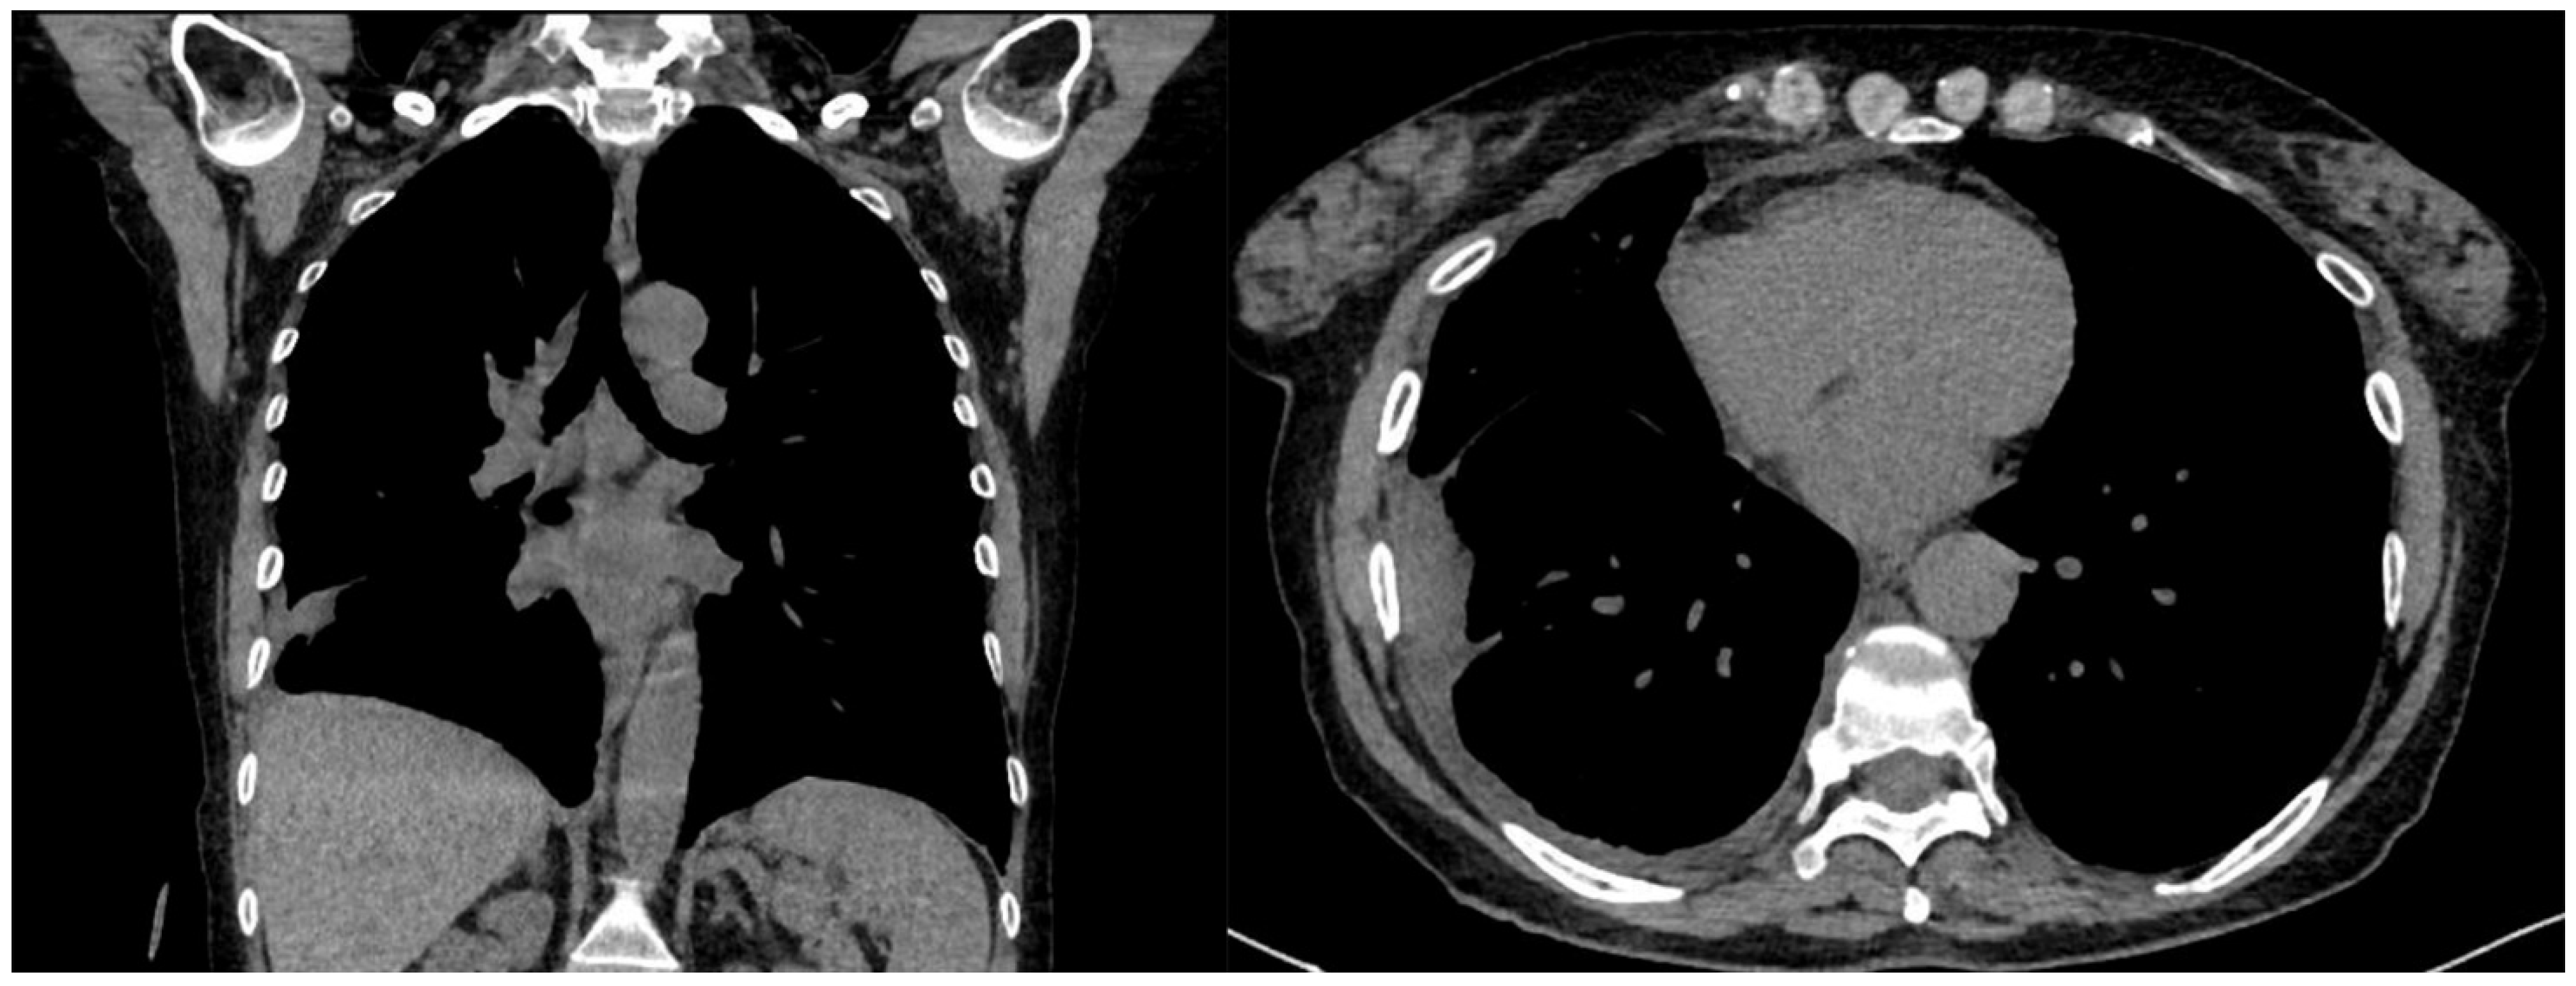

A 60-year-old Caucasian man was admitted to our hospital with a history of worsening pain at the base of the right hemithorax and feeling generally unwell for over one month. The patient’s past medical history included coronary heart disease, with a percutaneous coronary intervention in 2014. He smoked a half-pack of cigarettes per day for 40 years and had no history of respiratory disease. The CT chest scan showed a fluid collection in the medium–lower parts of the right hemithorax with thickened walls and contrast enhancement (Figure 5). This collection appeared in continuity with further smaller fluid collections with thickened walls, contrast enhancement, and confluence and caused the complete atelectasis of the middle and lower lobes and the partial atelectasis of the upper lobe, as well as middle and inferior lobar bronchus occlusion.

Figure 5. Chest CT scan of the mediastinal window in the coronal (A) and axial (B) plane, showing fluid collection in the medium–lower parts of the right hemithorax (maximum axial dimeters of 19 × 13 cm; craniocaudal extension of 16 cm) with thickened walls and contrast enhancement. There is also a complete atelectasis of middle and lower lobes and partial atelectasis of the upper lobe.